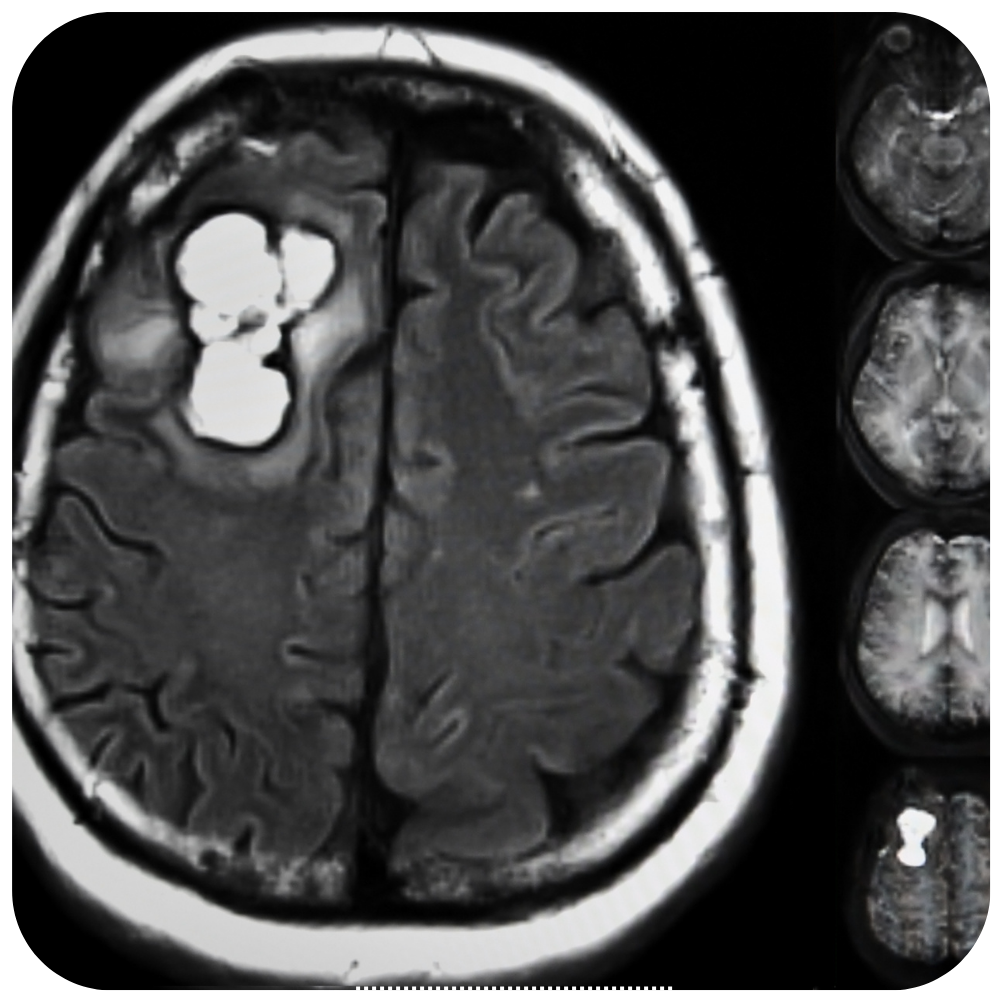

Craneotomía Operación en la que se extrae un pedazo del cráneo. Una craneotomía se realiza para que los médicos puedan extraer un tumor o tejido anormal del cerebro. También se puede realizar para extraer sangre o coágulos del cerebro, aliviar la presión en el cerebro después de una lesión o…